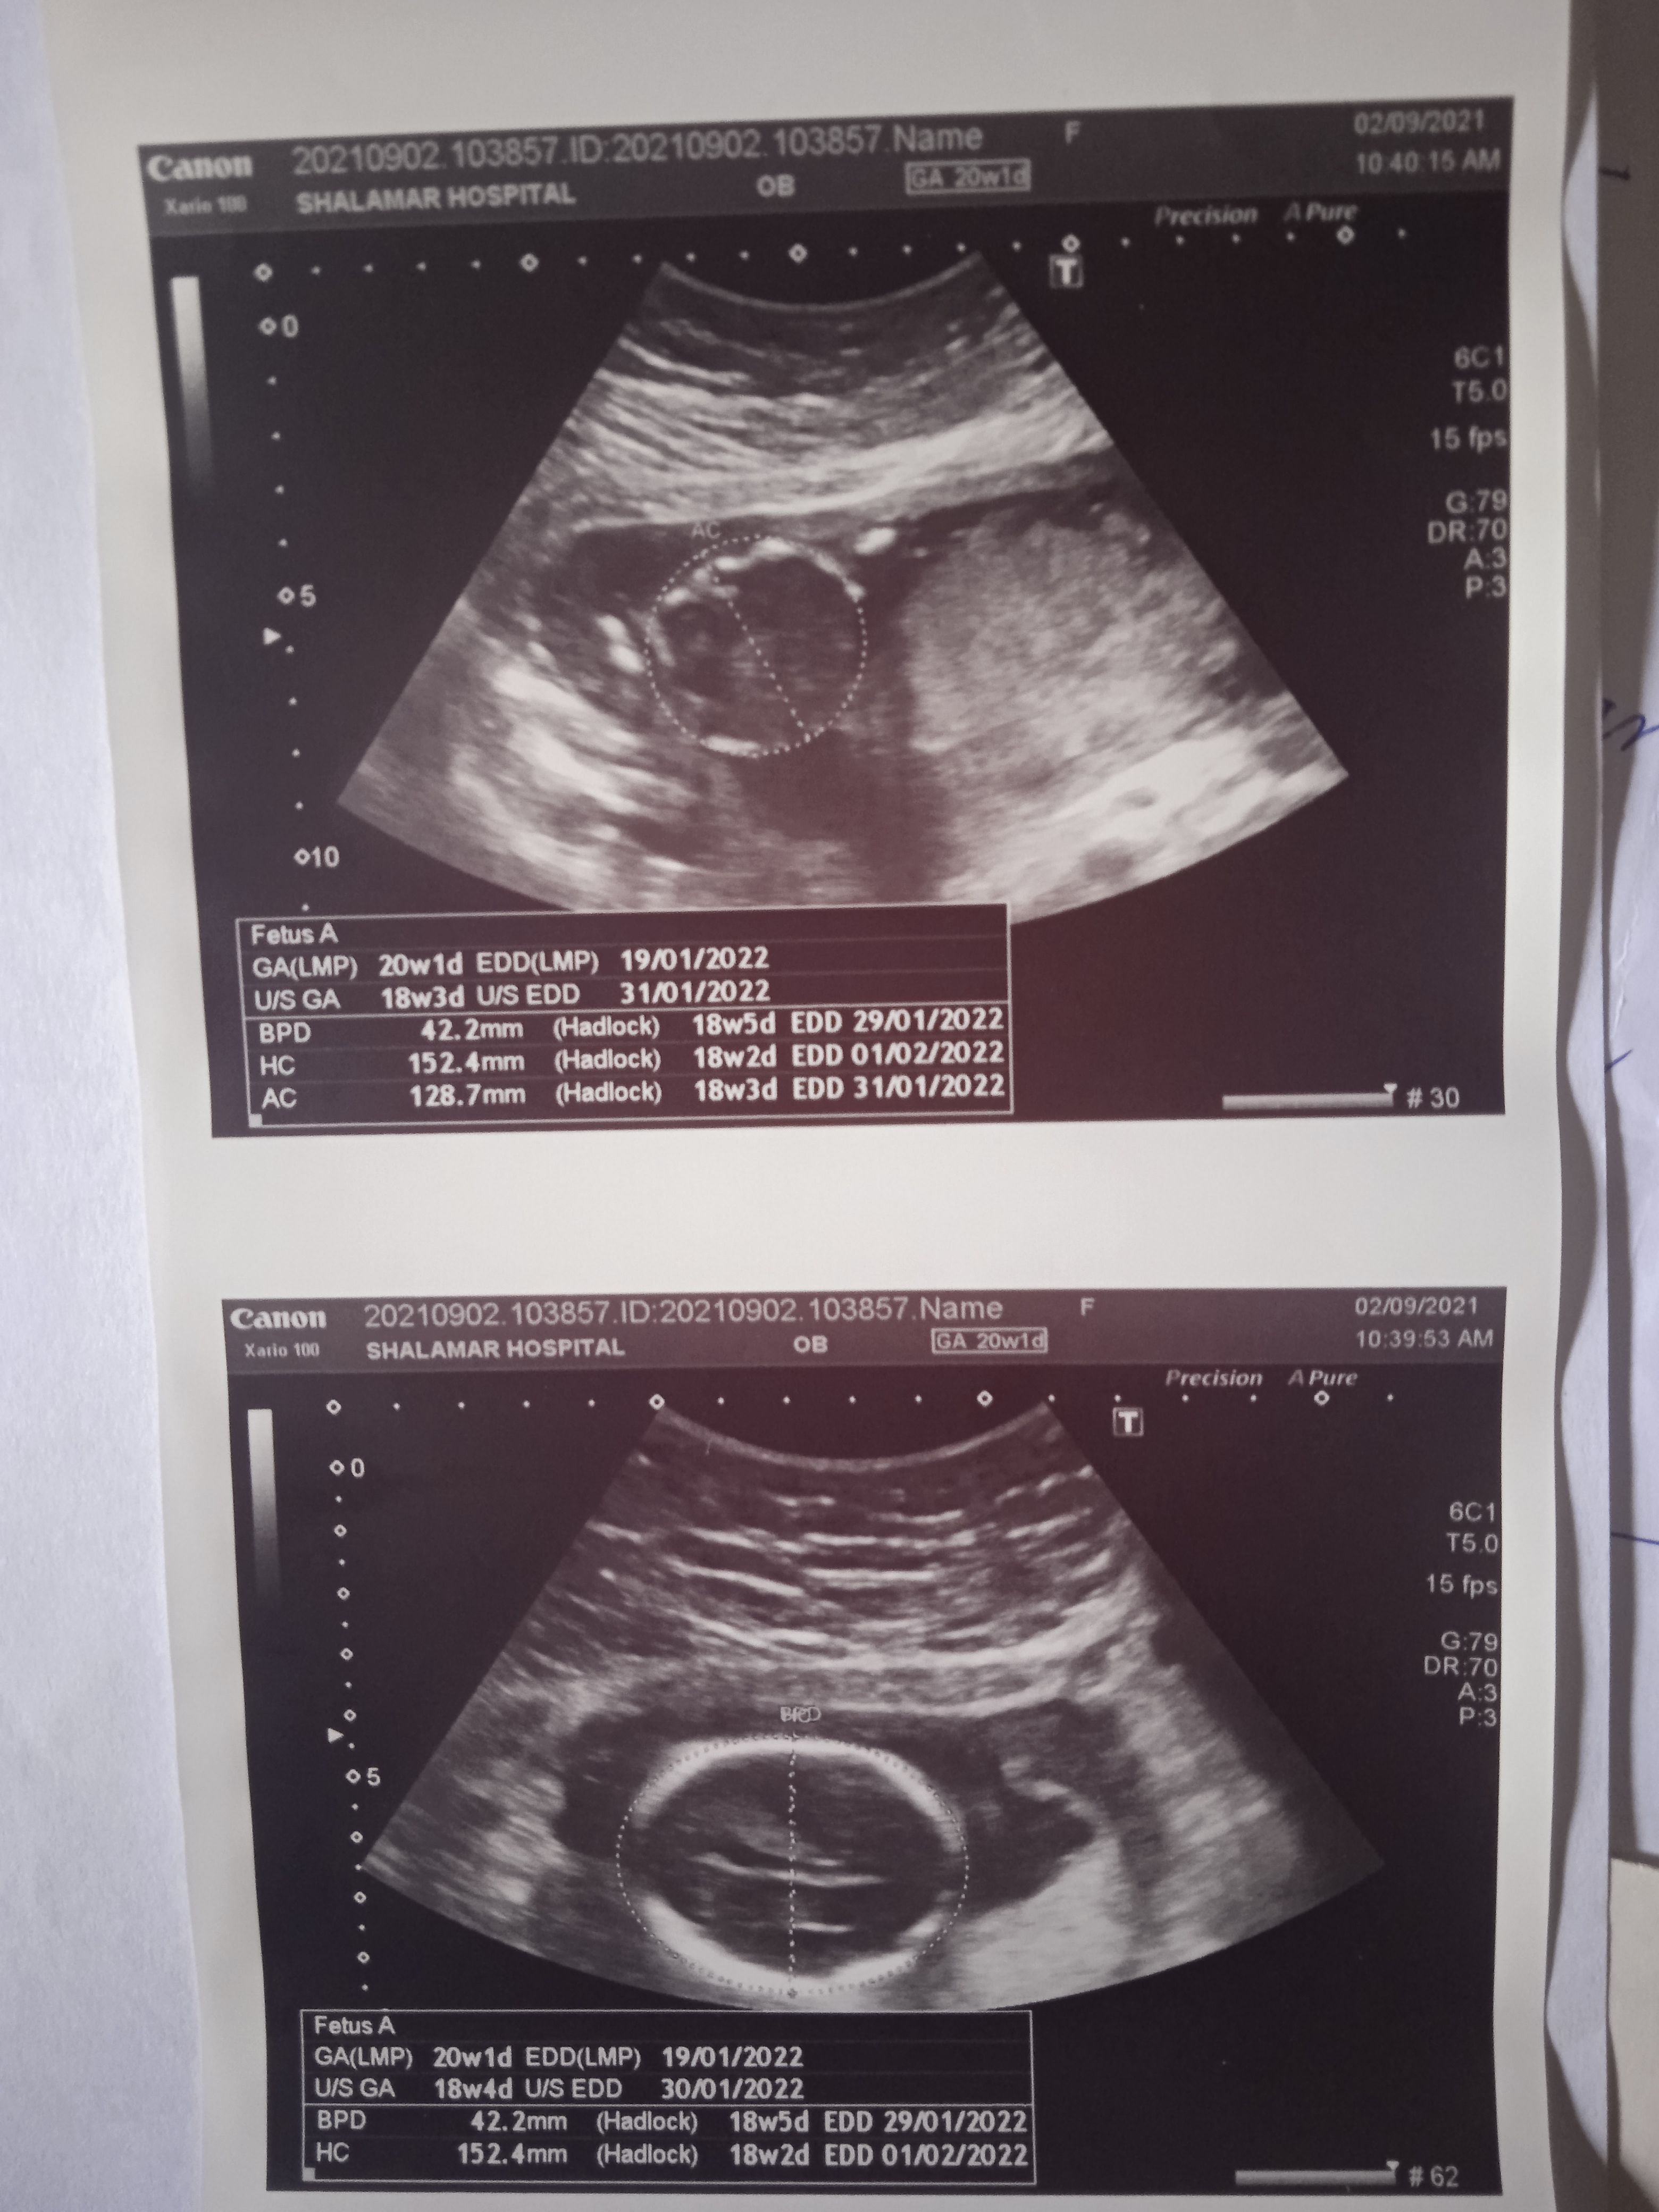

Please check the pics below.

And tell me about my baby gander.

Here is my altrasound report

Plz tell me gender of my baby plz

Here is altrasound report

Please see that report.

Anyone please let me know my baby's gender

I have uploaded my altrasound report